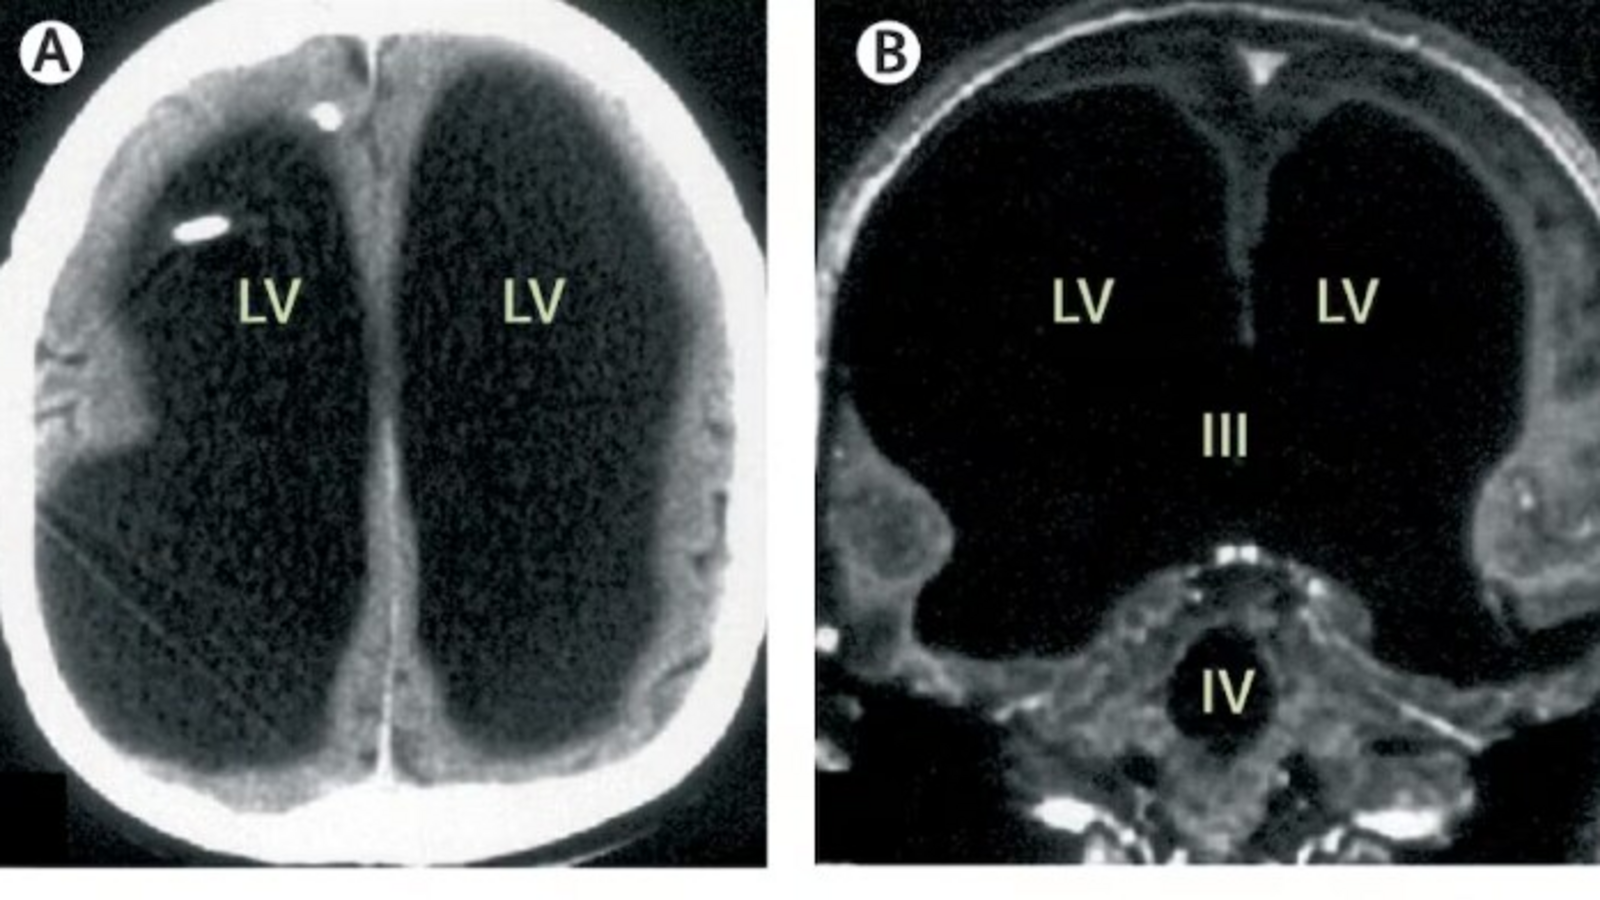

A rare medical case, first described in The Lancet in 2007, highlights the brain’s remarkable adaptability and neuroplasticity. Despite losing 90 percent of his brain, the then 44-year-old French man was reportedly able to lead a relatively…